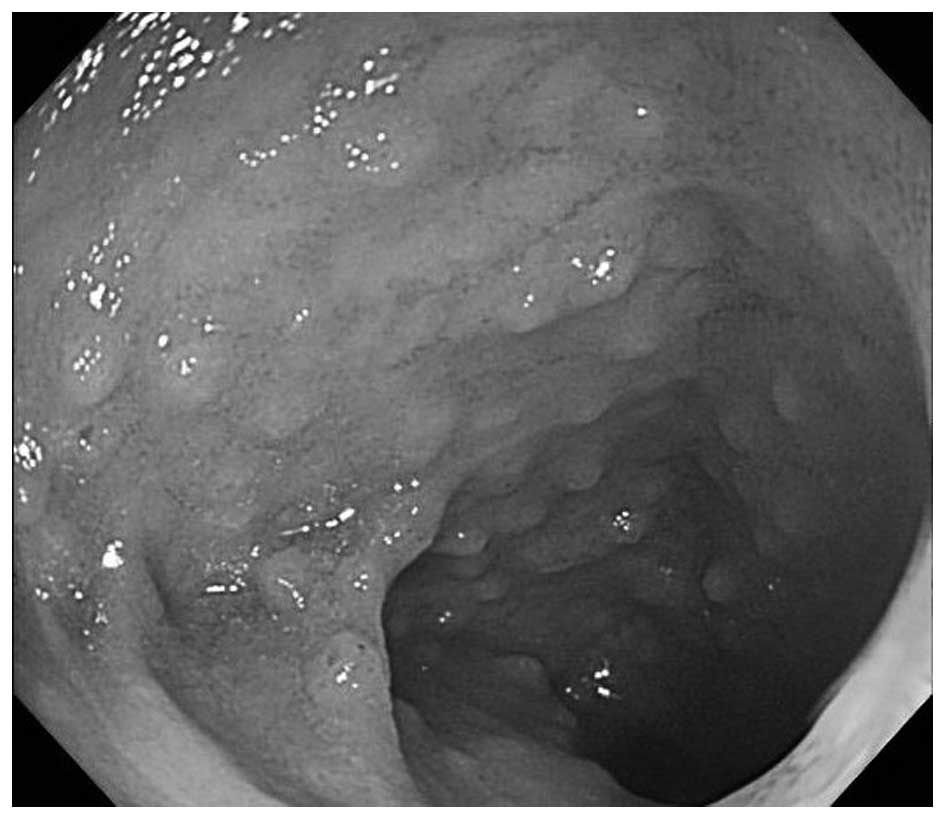

A 24-year-old man with an unremarkable medical history was referred to Onomichi General Hospital (Hiroshima, Japan) as a result of melena and anemia in 2004. An upper gastrointestinal endoscopy in 2004 revealed multiple edematous polyps around the fundus of the stomach (Fig. 1). Histological examination revealed a hyperplastic and disorganized foveolar epithelium, and an edematous lamina propria with infiltration of inflammatory cells, and the histological diagnosis was hyperplastic polyps. The patient began taking a proton-pump inhibitor and iron supplements, and he underwent an upper gastrointestinal endoscopy annually. The polyps appeared around the fundus in 2004 and had gradually progressed to the entire stomach in 2014 (Fig. 2). The number and size of the polyps had also increased. Endoscopic mucosal resection was performed frequently due to bleeding from the polyps. It was difficult to control the progressing anemia by non-surgical treatment, and, in 2014, histological examination revealed for the first time that the benign polyps were adenocarcinoma. Surgical treatment was therefore performed. At the time of surgery, the patient was 171 cm tall and weighed 62.5 kg. No skin lesions or loss of hair, which is characteristic of Cronkhite-Canada syndrome, was exhibited. Laboratory data demonstrated mild anemia (hemoglobin, 9.6 g/dl), but neither hypoproteinemia nor elevation of tumor markers, including carcinoembryonic antigen and carbohydrate antigen 19–9 was observed. With respect to the patient's family history, the patient's mother had succumbed to colon cancer in her 50s and his cousin had succumbed to an unknown primary cancer in his 30s. Colonoscopy revealed no specific findings. Enhanced computed tomography revealed that the stomach wall was edematous with enhanced thickening from multiple polyps (Fig. 3). An upper gastrointestinal series revealed that multiple polypoid lesions were limited to the entire stomach and were not present in the small intestine (Fig. 4). The patient underwent laparoscopy-assisted total gastrectomy with Roux-en-Y esophagojejunostomy. The resected specimen revealed numerous diffuse polyps throughout the entire stomach (Fig. 5). Microscopic findings revealed a hyperplastic and disorganized foveolar epithelium with an atypical nuclear shape. Enlargement of the nucleolus was also observed, and the patient was diagnosed with well-differentiated adenocarcinoma. A total of three lesions of early gastric cancer, and no lymph node metastasis were detected. Immunohistochemical staining revealed that the specimen was positive for p53 and carcinoembryonic antigen and exhibited a high index of mindbomb E3 ubiquitin protein ligase 1 (Fig. 6). The postoperative course was uneventful, hemoglobin level returned to the normal range, and the patient experienced no recurrence over a 1 year follow-up.

Figure 1.

Upper gastrointestinal endoscopy in 2004. An upper gastrointestinal endoscopy from 2004 revealed small polyps only around the fundus.